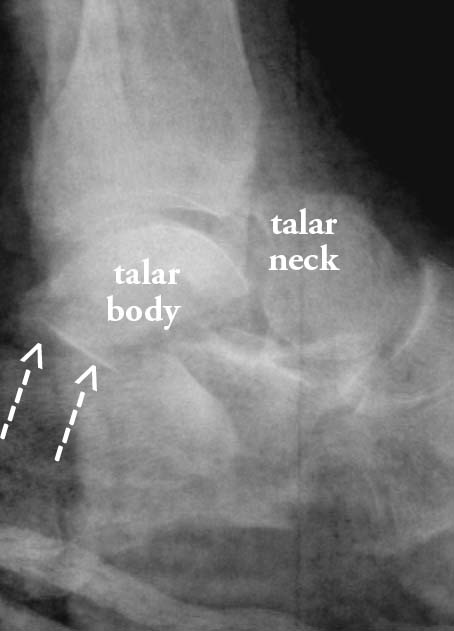

A paratrooper was taken to the hospital complaining of bad pain in the right foot caused by improper and forceful landing on her heel. Upon arrival at the hospital her injured foot was swollen, deformed and held rigid. AP, lateral and oblique x-rays were done, and an undisplaced fracture of the talar neck was shown. The orthopedic surgeon ordered a split plaster of Paris that should be reapplied when swelling settles.

1. How would the talus get fractured as a result of a fall on the heel?

The upward thrust of the calcaneus against the talus and tibia may fracture the talus.

2. What other bones may fracture from such trauma?

Calcaneus and lower end of the tibia.

3. In this case, the surgeon should do a special examination of the vessels in the vicinity of the fractured talus. Which vessel is of importance in this respect?

The dorsalis pedis pulse is important to be checked in such cases.

4. What complication may arise from such a fracture?

Avascular necrosis and non-union.